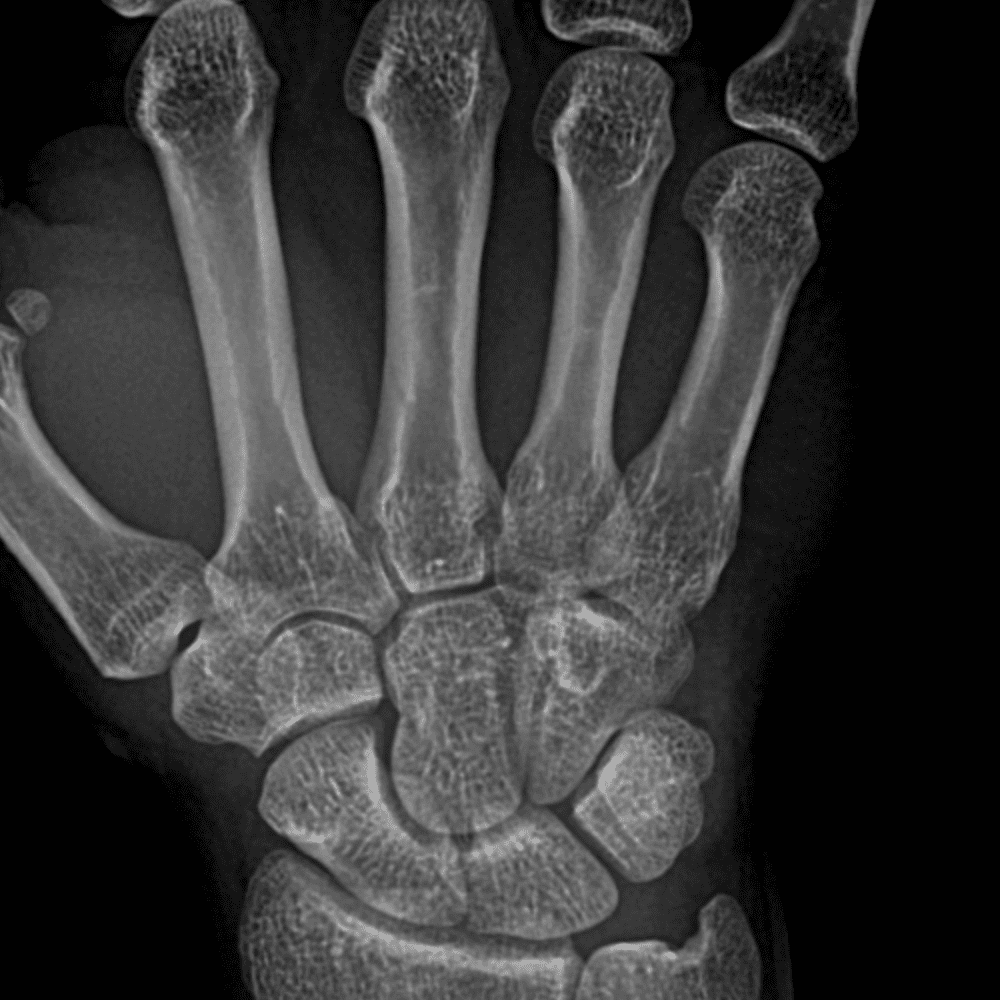

Simuliert den Dienst durch subtile oder schwierige Fälle und einige Normalbefunde.

30 Fälle